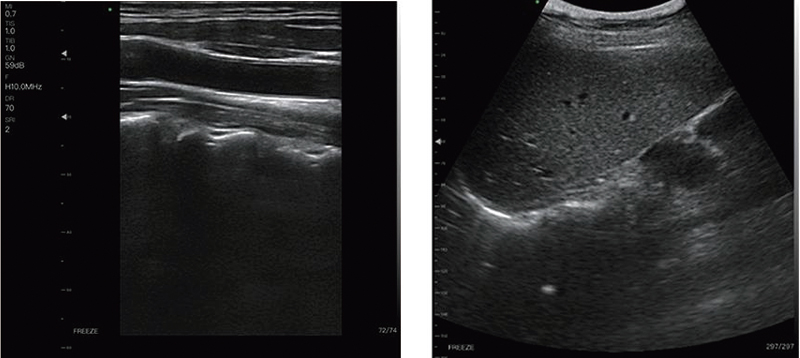

Application Sites: Abdomen, Superficial, Lung, Cardiac

- Emergency Inspection: ER, iCU, Wild First Aid, Battle Field Rescue.

- Preliminary Examination: Ward inspection, primary clinic examination, medical examination, health screening, home care, family planning, etc.

- Visualization Tools: invasive intervention guide, surgical and therapy guidance.